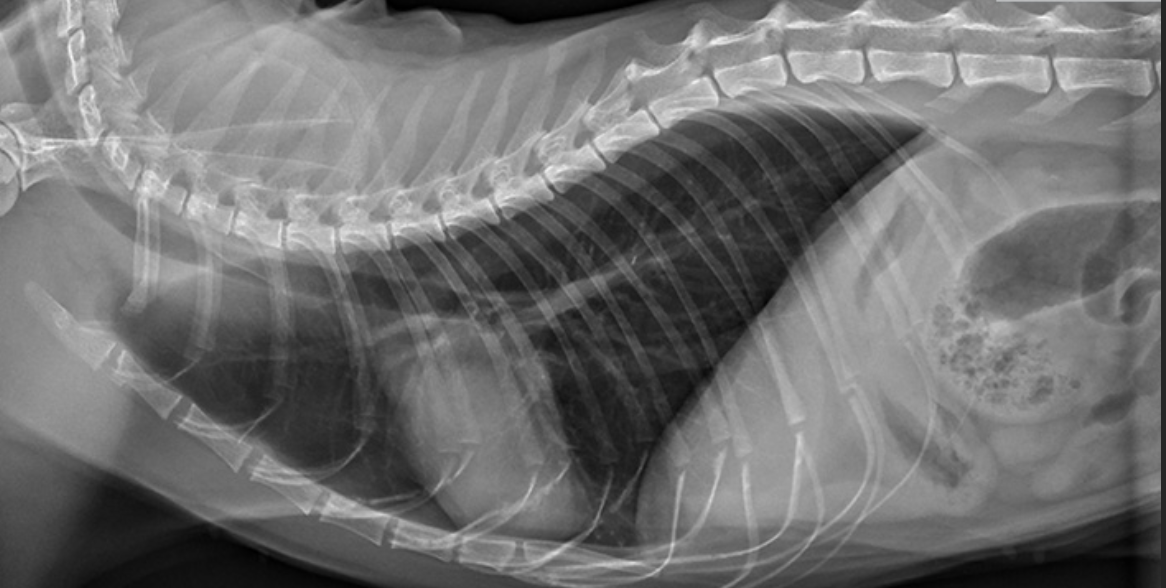

Les radiographies thoraciques peuvent être assez caractéristiques d'une atteinte bronchique mais peuvent aussi être complètement normale chez un chat asthmatique.

Elles permettent néanmoins d'écarter une tumeur, un épanchement pleural ou une infection.